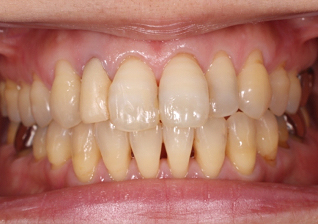

右上の歯の前から2番目を抜歯し、即時にインプラントを施した前歯部・審美領域の治療

- 被せ物が脱離した右上2は歯根破折をしており、保存不可能と判断されたため抜歯と同時のインプラント埋入を計画。抜歯と同時にインプラント埋入。そのインプラントの生着を待って上部構造の装着を行なった

- 435,000円(税別)

- 3ヶ月